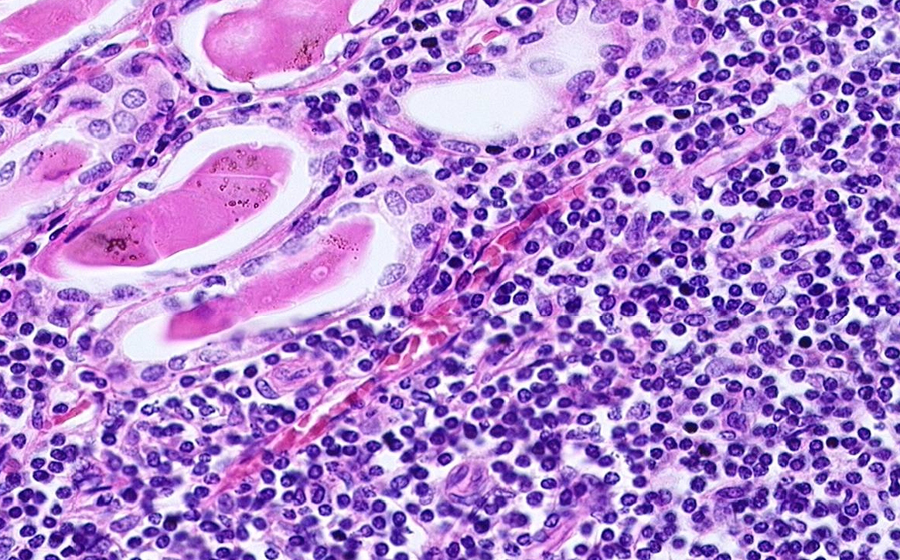

Image 5 - 200X

Slide 3 - Image 5